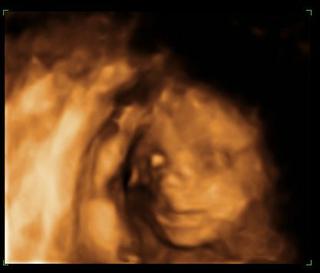

@rianka7 ano u palla robia 4d utz stal po starom okolo 2000sk. bola som u neho na morfologickom a neodporucam.. mna osobne sa dost dotkol, kedze som mala robeny utz viacerymi lekarmi a nikto nemal problem pozriet, krasne bolo vsetko vidiet a on mi povedal,ze nevidi,lebo mam vela tuku.. pre porovnanie foto od palla to oranzove a foto zo 4d z KE . bola som u dr.Dankovcika cena zhruba to iste, zazitok neskutocny mam cd s fotkami a videami z utz..